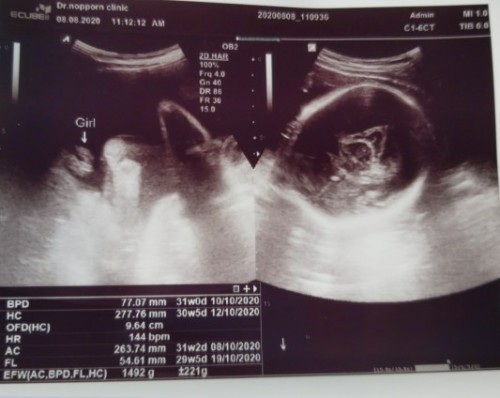

เพศลูก

แบบนี้ผู้หญิงแน่นอนใช่มั้ยคะแม่ๆ

ในใบบอกว่าผู้หญิงคะ Girl